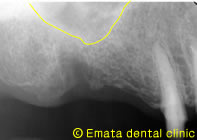

CT画像

患者さんは、右上奥歯をインプラント治療を希望されて来院された62才の男性の方です。上顎洞底の位置が低く、CT撮影で外側の骨も喪失してることがわかりました。奥歯の上には上顎洞という空洞(黄色の矢印の線)がありこのままではインプラントが上顎洞内に突き抜けてしまうためインプラントの手術ができません。